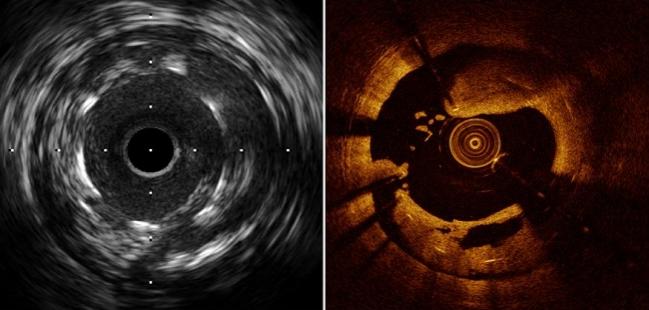

Photo Credit: Guagliumi G. State-of-the-art review: intravascular imaging and physiology to evaluate stent thrombosis and restenosis. Presented at: TCT 2017. November 1, 2017. Denver, CO.